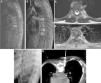

ResultadosEn el período 1995-2014 se trataron 83 pacientes (45% mujeres, edad mediana 66años) con diagnóstico de espondilodiscitis (confirmación microbiológica en el 67,4%). Existió déficit neurológico preoperatorio en el 44,5%. El nivel más frecuentemente afectado fue el dorsal (54,2%). Los principales gérmenes aislados fueron Mycobacterium tuberculosis (22,9%), Staphylococcus aureus (20,5%) y SARM (7,2%). Se intervinieron 81 pacientes mediante: laminectomía simple y/o biopsia (22,2%), laminectomía, desbridamiento y artrodesis posterior (43,2%), y desbridamiento y fijación anterior (34,5%). El 86,7% de los pacientes intervenidos obtuvieron buena evolución postoperatoria (mejoría sintomática o del déficit). Se estabilizaron 7 pacientes y empeoraron 2. Aparecieron complicaciones en 35 pacientes, fundamentalmente derrame pleural (9), anemia (7) y necesidad de reintervención y desbridamiento (7). La mediana de estancia postoperatoria fue de 14días. Tras un seguimiento medio de 8,5 meses se consideraron curados 46 pacientes, 10 presentaron secuelas, se perdieron 22 pacientes y 5 fallecieron. La cirugía no motivó reingresos.

ResultsFrom 1995 to 2014, 83 patients (45% females, median age 66) with spondylodiscitis were treated. Microbiological confirmation was obtained in 67.4%. Forty-four percent of patients presented with neurological defect. The most common affected level was thoracic (54.2%). The most frequent isolations were Mycobacterium tuberculosis (229%), Staphylococcus aureus (20.5%) and MRSA (7.2%). Eighty-one patients underwent surgery: simple laminectomy and/or biopsy (22.2%), debridement and posterior fixation (43.2%) and debridement and anterior fixation (34.5%). Improvement of pain or neurological defect was achieved in 86.7% of the patients; 7 patients stabilized and 2 worsened. Complications occurred in 35 patients, mainly pleural effusion (9), anaemia (7) and need for re-debridement (7). Median postoperative stay was 14days. After a median follow up of 8.5 months, 46 patients were considered completely cured, 10 presented sequelae, 22 patients were lost and 5 patients died. No readmissions occurred because of the infectious episode.